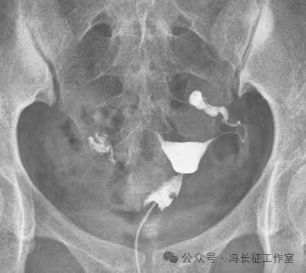

造影显示2个弹簧圈紧实固定在输卵管间质部和峡部近段。弹簧圈两端由于弹性回缩力的回缩呈C形,卡在输卵管内壁上,完全封闭管腔,造影剂未能进入通过栓塞段,栓塞段输卵管远端未能显影。

微信图片_20240223171446(7).jpg